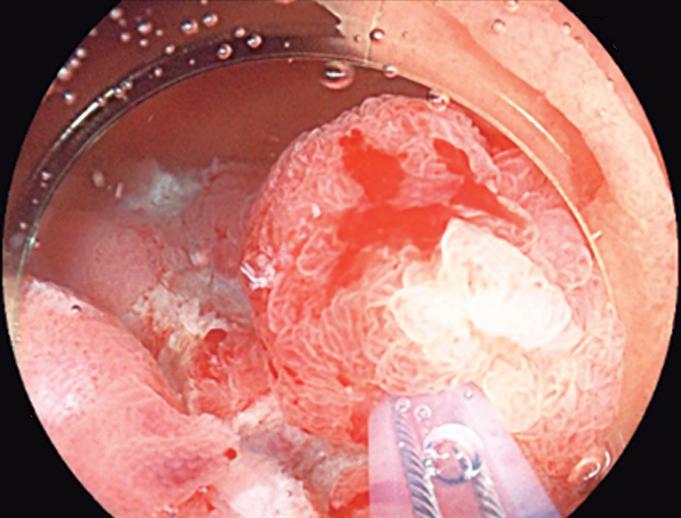

Evaluación endoscópica e histológica

La endoscopía superior es un procedimiento fundamental para el diagnóstico, la evaluación de la respuesta al tratamiento y el monitoreo a largo plazo de la actividad de la EEo. Los hallazgos endoscópicos típicos incluyen edema (reducción de vascularidad), anillos esofágicos fijos, exudados blancos, surcos longitudinales, estenosis, estrechamiento de la luz esofágica, friabilidad de la mucosa (mucosa en papel crepé) y una consistencia firme de la mucosa al realizar biopsias (signo de “tracción" o "resistencia”) en pacientes con fibrosis (Figura 1). Estos hallazgos no son patognomónicos y no constituyen un criterio diagnóstico; sin embargo, cuando se evalúa de forma cuidadosa, en la gran mayoría de los casos se pueden observar.19-21

Es imperativo llevar a cabo una exploración endoscópica minuciosa en todos los casos de sospecha de patología esofágica. En el contexto de la EEo, esto requiere dedicar un tiempo adecuado a la visualización completa del esófago tras la intubación, evitando desplazar o raspar los exudados, insuflando adecuadamente el esófago, eliminando cuidadosamente mucosidad, saliva o detritus, y evaluando el calibre esofágico. Esta evaluación puede incluir la retroflexión en la unión gastroesofágica para estimar el diámetro de las estenosis en dicha región.22

Un elemento fundamental en la evaluación de la EEo es la aplicación del puntaje de referencia endoscópica para la esofagitis eosinofiílica (EREFS por sus siglas en inglés: Eosinophilic Esophagitis Endoscopic Reference Score).20 El acrónimo EREFS también refleja las cinco características endoscópicas principales de la EEo: Edema, anillos esofágicos (Rings), Exudados, surcos longitudinales (Furrows) y estenosis (Stricture). Estas características se clasifican según su severidad mediante un sistema de puntuación que oscila entre 0 y 9, considerándose la región esofágica con la alteración más marcada. El EREFS cuenta con validación interna y externa, y ha demostrado una elevada capacidad para diferenciar la EEo de otras patologías no relacionadas en poblaciones pediátricas y adultas, además de correlacionarse con la respuesta terapéutica.23-25 Por estos motivos, el EREFS constituye un sistema estandarizado para la evaluación

En el panel A se observa un esófago con edema difuso y pliegues longitudinales; en el panel B se aprecia edema con pliegues y exudados blanquecinos; en el panel C se evidencia un estrechamiento luminal acompañado de anillos esofágicos y exudados; y en el panel D se muestra un desgarro mucoso posterior a la dilatación con bujía de Savary, hallazgo esperado tras este procedimiento terapéutico.

Figura 1. Características endoscópicas de la esofagitis eosinofílica